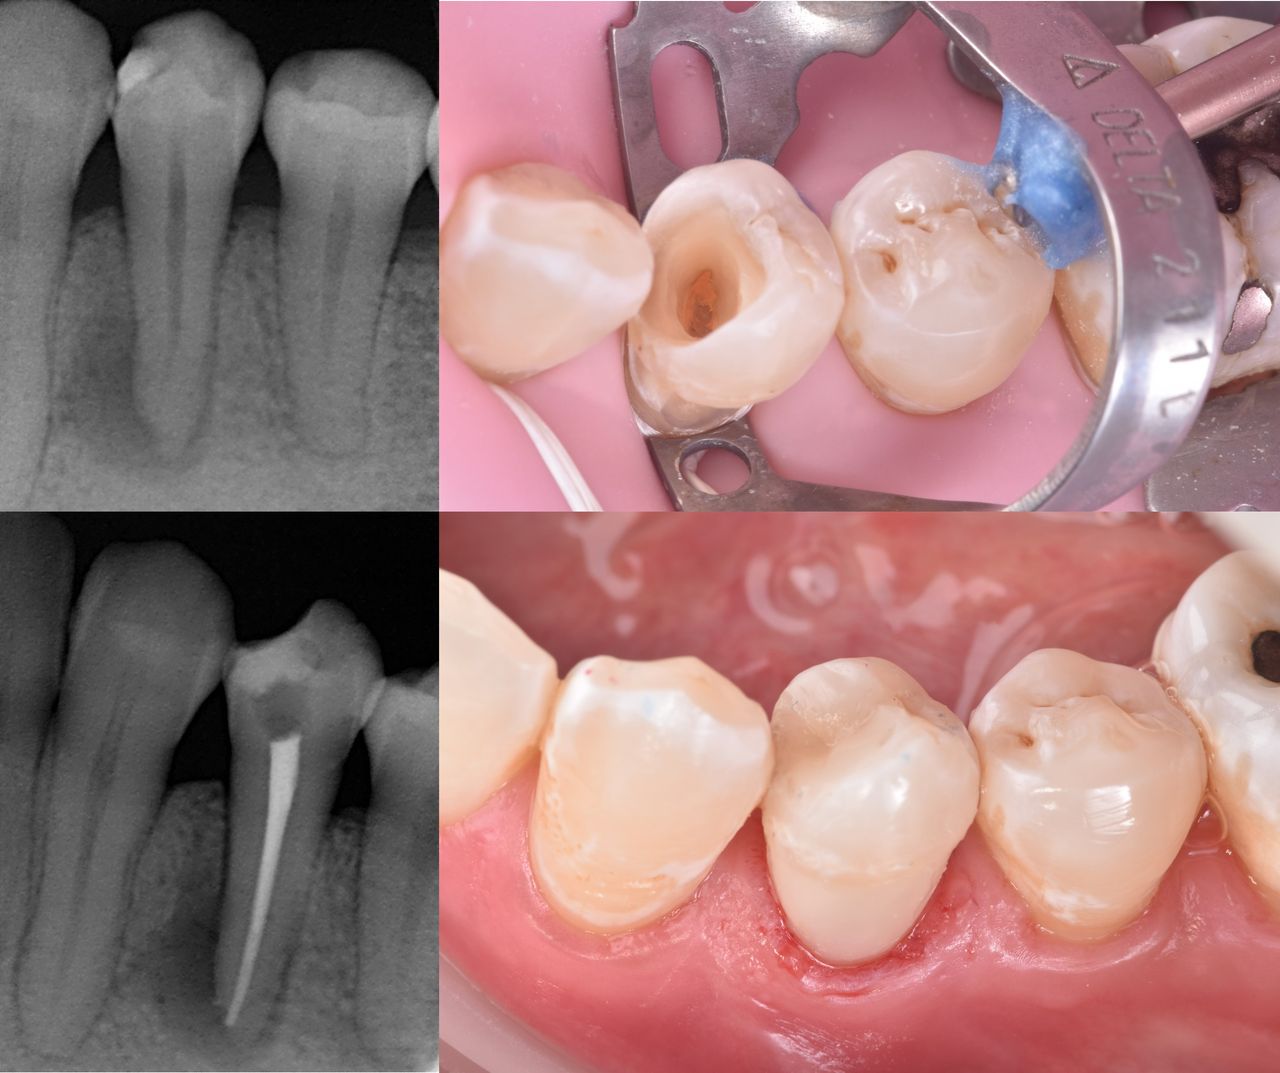

Cirujano Dentista - Especialista en Endodoncia - Pontificia Universidad Católica de Chile

Hola, soy la Dra. Constanza Leiva, me dedico a ayudar a mis pacientes a dejar atrás el dolor y a conservar sus dientes naturales con tratamientos modernos, cómodos y seguros.

En la clínica trabajamos con tecnología de última generación: lupas de magnificación para mayor precisión, anestesia digital para que el procedimiento sea prácticamente indoloro, y equipos que me permiten ofrecerte resultados predecibles y de alta calidad.

• Endodoncia